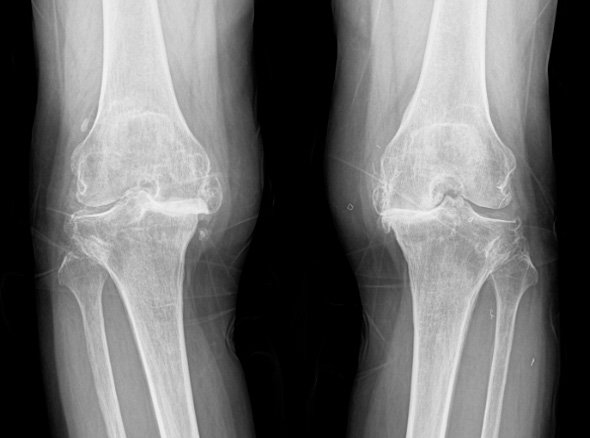

노화로 인해 연골이 닳아 통증,

운동 제한이 발생하는 경우

(계단 오르내리기, 구부리기, 쪼그려 앉기 등)

자가면역질환으로

관절 염증이 심한 경우

골절이나 심한 관절 손상으로

정상적인 기능이 어려운 경우

혈액 공급 장애로 인해

관절 조직이 괴사된 경우

퇴행성관절염은 치료의 시기가 매우 중요합니다.

한번 진행이 시작되면 피하기가 어려워 치료가 빠를수록 진행을 최대한 늦출 수 있습니다.

인공관절 수술은 진행이 악화되어 더 이상 약물로 치료할 수 없을 때 시행하는 최후의 방법입니다.